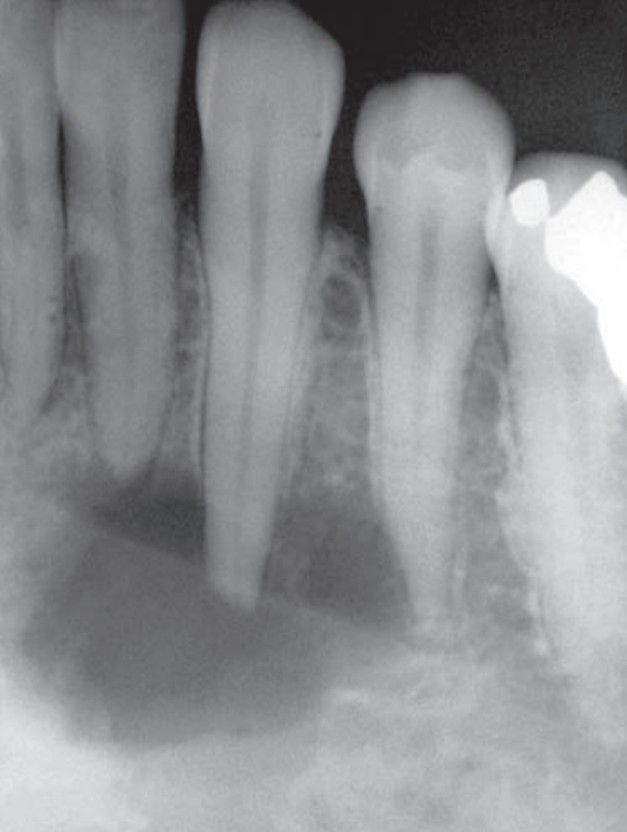

Central giant cell granuloma

Central giant cell granuloma of anterior mandible.